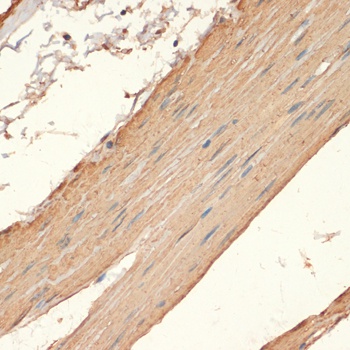

IHC: Formalin-fixed, paraffin-embedded human colon carcinoma stained with SMMHC antibody (MYH11/923).

IHC: Formalin-fixed, paraffin-embedded human Leiomyosarcoma stained with SMMHC antibody (MYH11/923).

IHC: Formalin-fixed, paraffin-embedded human breast carcinoma stained with SMMHC antibody (MYH11/923).

IHC: Formalin-fixed, paraffin-embedded human angiosarcoma stained with SMMHC antibody (MYH11/923).